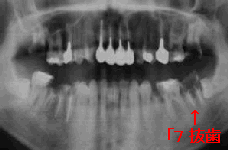

21歳 女性 │5象牙質カリエス

初診時 X線写真(パノラマより抜粋) 本人の自覚症状は全くなし

清掃状態は比較的良好ではあるが、全体にカリエスが多く、抜髄を含む治療済みの歯が目立つ。 肉眼所見では、咬合面のピンホールカリエスで一見軽傷と思われるが、いずれの歯も象牙質 部分のカリエス進行が著明。その中でも│5の象牙質カリエスは思わず感心してしまう ほどの見事さであった。

極力歯髄保護の方針で治療を行ったが、│5はタービンを使った瞬間に露髄してしまい やむなく抜髄。治療に際しても歯髄炎症の所見は全くなく、改めて感心しながらの治療となった。

スポーツ選手ということもあって、患者さんの健康状態・免疫抵抗力ともに並外れたものが感じ られる。カリエス罹患部と歯髄とのあいだに、一切健全牙質がないようにも思われるにも かかわらず、全くといって良いほど歯髄炎症が存在しないのは興味に値する。 歯髄炎や象牙質知覚過敏症との関わりから重要なヒントを与えてくれる症例ではあるが、今のところ 明解な回答がえられない。